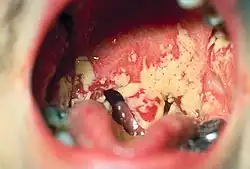

Pseudomembranous candidiasis of the posterior mouth and oropharynx

• Oral candidiasis is by far the most common fungal infection that occurs in the mouth. It usually occurs in immunocompromised individuals. Individuals who have undergone a transplant, HIV, cancer or use corticosteroids commonly develop candida of the mouth and oral cavity. Other risk factors are dentures and tongue piercing. The typical signs are a white patch that may be associated with burning, soreness, irritation or a white cheesy-like appearance. Once the diagnosis is made, candida can be treated with a variety of anti fungal drugs.[25]